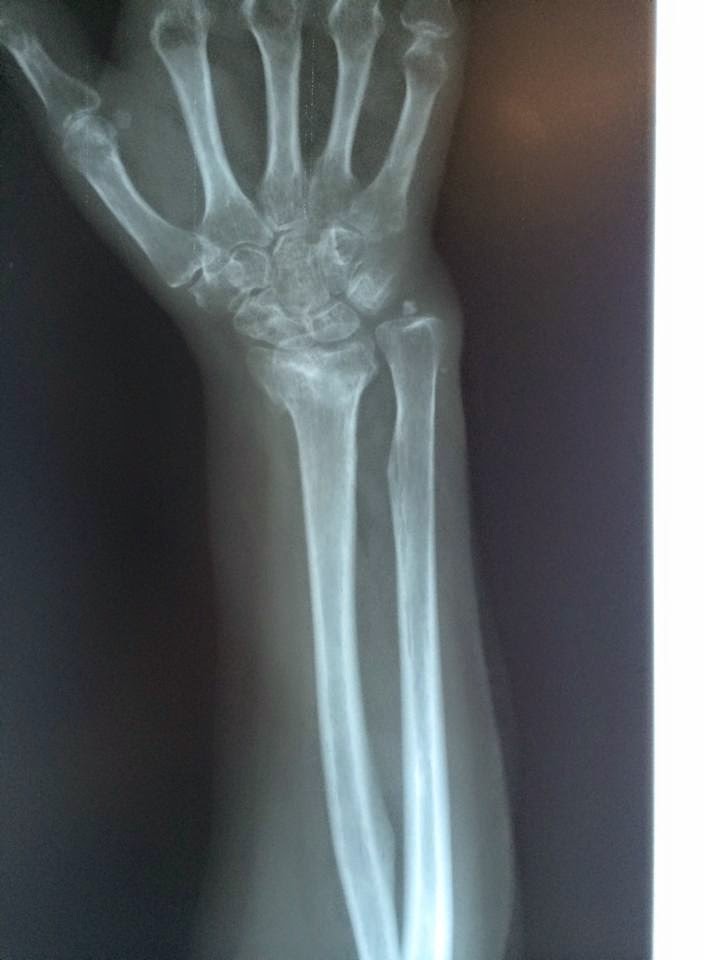

Fracturas d radio distal:muchas veces primera señal de osteoporosis http://t.co/2mjXDIDKJm http://t.co/uVgmS5bUlE

— tutraumatologo (@tutraumatologo) marzo 26, 2015